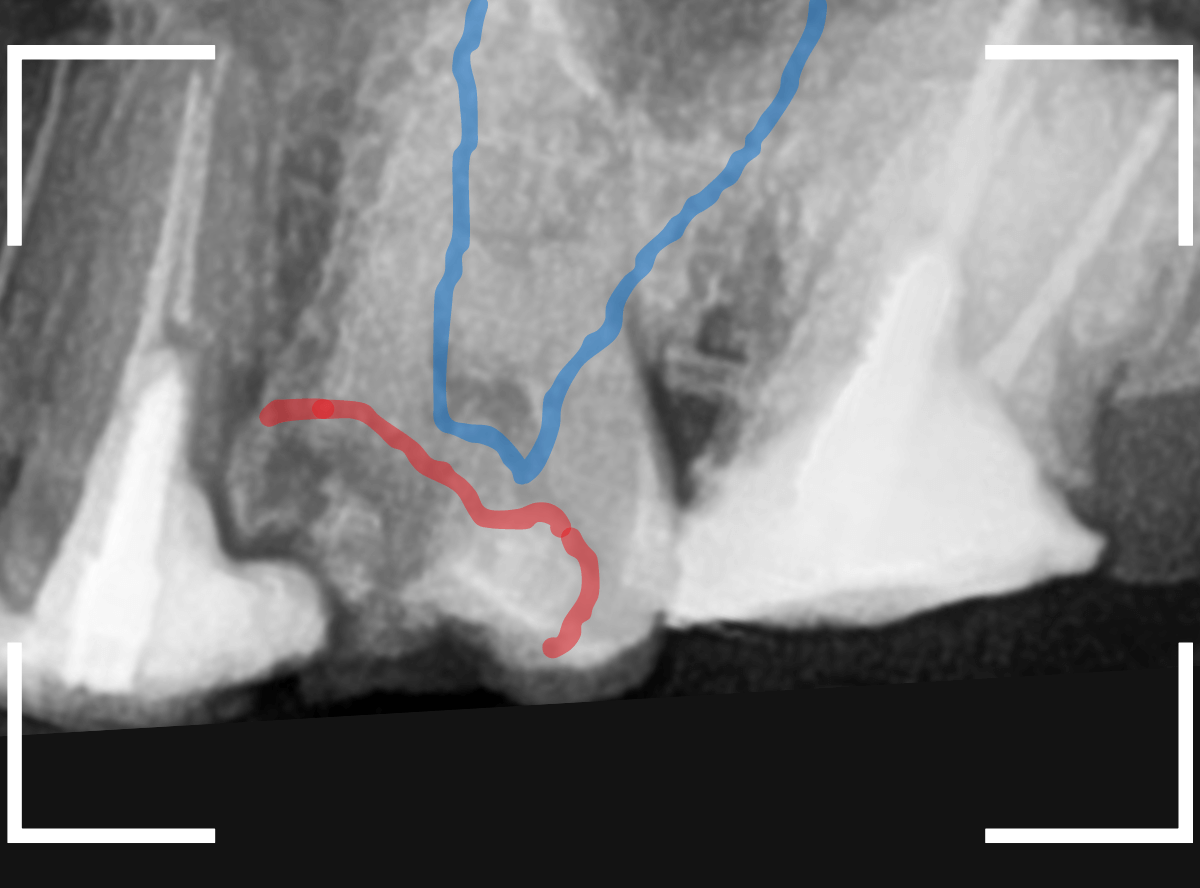

Case.16 レジンの下の深い虫歯2

虫歯の治療希望で来院された患者さんです。

レジンが欠けて大きな穴が空いているのが見えます。

このような場合は、中で虫歯が進行している事が多いです。

(レジンの中で虫歯が進行してレジンに穴が空いた、レジンが欠けたのを放置して虫歯が進行したパターンなどがあります)

レントゲン写真で確認します。

青い線が歯の神経です。

赤い線が虫歯と思われる部分です。

思った通り、神経に達してしまいそうな大きな虫歯です。

患者さんには、神経を取る治療が必要な可能性が高い事を説明します。

治療開始です。

まず、慎重にレジンを除去します。

レジンの中の虫歯治療で難しいのは、レジンが歯と同じ色をしているために、歯なのかレジンなのか見分けがつきにくい時がある事です。

この写真でも、レジンがまだ残っているのがわかるでしょうか?

白い〇の部分です。

レジンを全て除去しないと、その下の虫歯を取り残してしまいます。

う蝕検知液で、虫歯の部分を判別しても、レジンが残っていると、わかりづらいです。

慎重にレジンを除去すると、歯の神経が顔を出してきました(露髄)。

レジンを除去したところでもう一度染め出しをしてみます。

神経の周りも虫歯で真っ赤に染まります。

露髄した部分が広がらないように、慎重に虫歯を除去しました。

幸い、それ以上広がる事はありませんでしたので、なんとか神経が残せる可能性が高いです。

お薬とセメントをつめて、経過観察します。

痛みが出ませんように・・・。